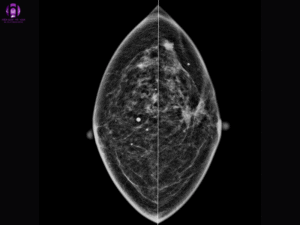

- Chụp nhũ ảnh: Là một loại phim X-quang ghi lại các biến đổi trong vú bằng cách chụp ảnh từ nhiều góc độ khác nhau.